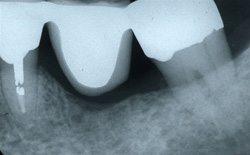

症例 A1 入れ歯治療適用症例

この症例は、歯周病により多くの骨量が吸収されているため抜歯しました。また、抜歯した両隣の歯の根のまわりも歯周病により骨量が少なく、そのため歯に中度の動きが認められました。もし、ブリッジ治療を適用した場合は、ブリッジ全体が徐々に動きが増すようになり、予後は大変不安となるでしょう。また、インプラントを埋めるための骨量の不足が考えられます。さらに多くの歯が動いているような場合は、インプラントだけ動きがないので天然の歯との不調和が生じ、噛む機能に障害が起こることになるでしょう。